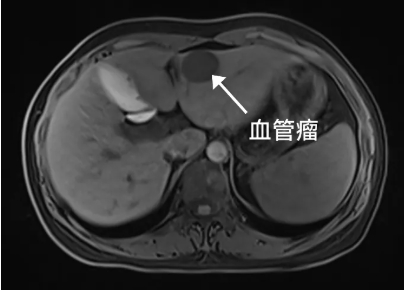

突然发现肝内长了一个

2.9cmm*2.7cm的血管瘤

“肝血管瘤名字里有个“瘤”,是不是就是得了肝癌的意思呀?”刘女士来到卢明柱主任专家门诊焦急地问。别怕,虽然名字里带有“瘤”字,但它并非恶性肿瘤,而是一种常见的肝脏良性肿瘤。“肝血管瘤,它是由肝脏内异常扩张的血管团组成。它通常生长缓慢,大多数情况下无症状,也不会恶变。通常在彩超体检中初步发现,进一步确诊往往需要增强CT或磁共振检查。但没有特效药物治疗。”卢明柱指出。

进一步确诊:CT、MRI增强扫描等影像学检查,结合医生专业评估。